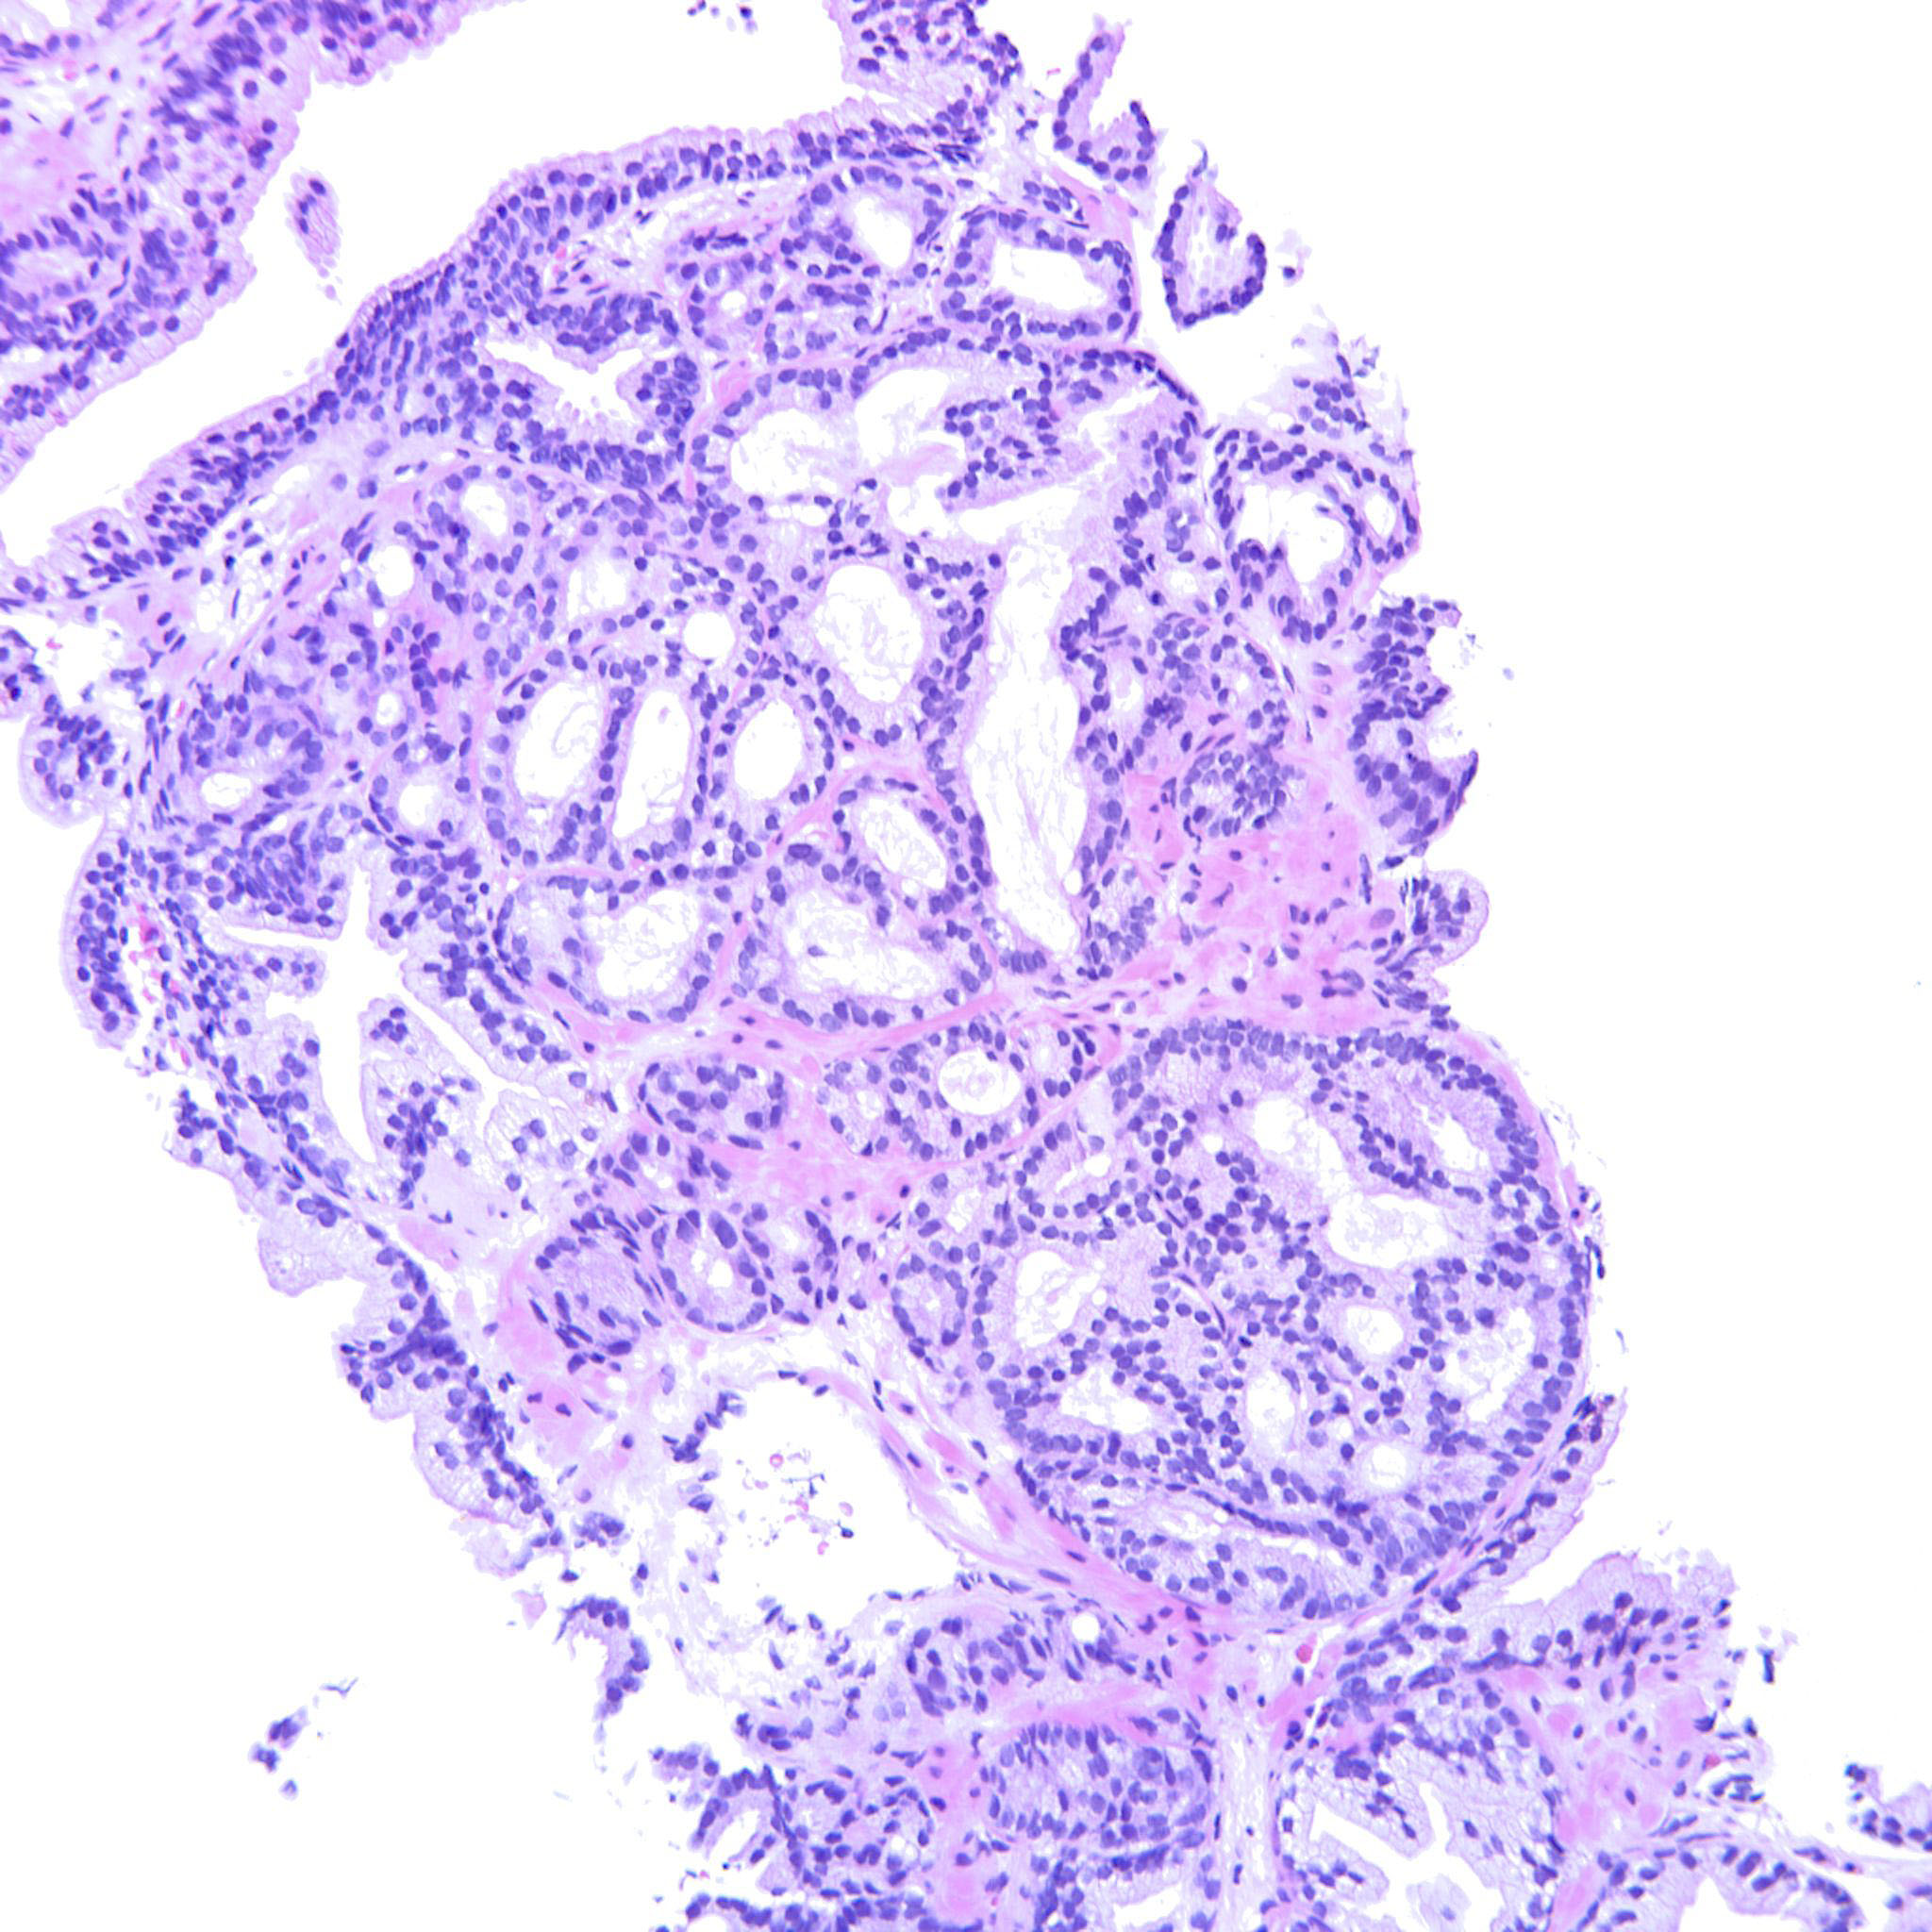

Prostate cancer grading

Case ID: 188